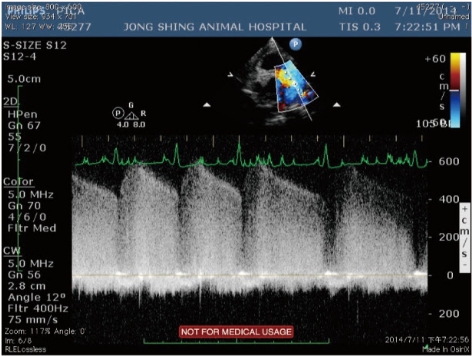

【圖一】左側胸壁短軸超音波斷面,可見一噴射狀血流由下行主動脈往肺動脈方向灌注, 流速疾快而呈現黃紅藍相間的馬賽克血流。

【圖二】 同圖一的超音波斷面,以cw都普樂模式,測量分流的血液流速,

可以偵測出典型的連續性梯型波形,最高流速為600cm/sec